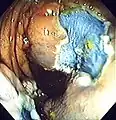

The first step is usually a digital rectal examination (DRE), to examine the tone of the anal sphincter and to determine if preparation has been adequate. A DRE is also useful in detecting anal neoplasms and the clinician may note issues with the prostate gland in men undergoing this procedure.[55] The endoscope is then passed through the anus up the rectum, the colon (sigmoid, descending, transverse and ascending colon, the cecum), and ultimately the terminal ileum. The endoscope has a movable tip and multiple channels for instrumentation, air, suction and light. The bowel is occasionally insufflated with air to maximize visibility (a procedure that gives the patient the false sensation of needing to take a bowel movement). Biopsies are frequently taken for histology. Additionally in a procedure known as chromoendoscopy, a contrast-dye (such as indigo carmine) may be sprayed through the endoscope onto the bowel wall to help visualize any abnormalities in the mucosal morphology. A Cochrane review updated in 2016 found strong evidence that chromoscopy enhances the detection of cancerous tumors in the colon and rectum.[56]